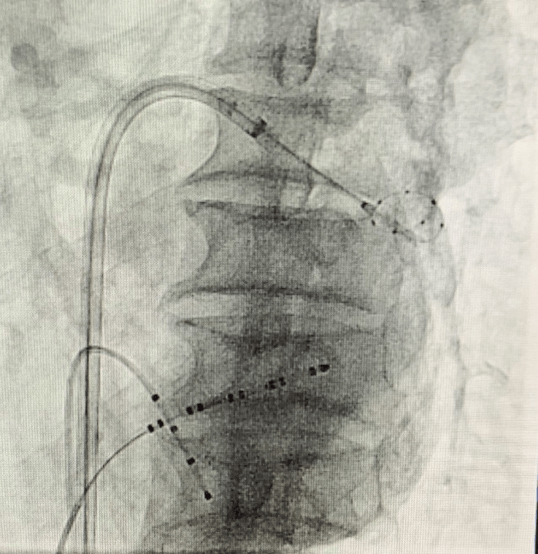

(手術(shù)過程)